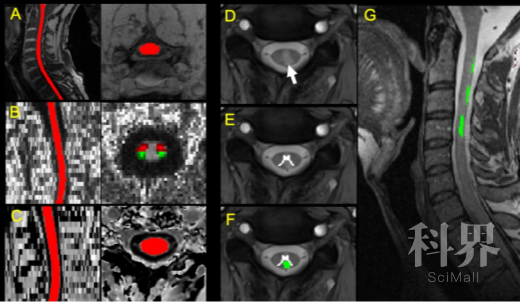

为了在体内探究降低AQP4膜定位对于缓解CNS edmema是否有效,作者在脊椎损伤(SCI)的大鼠模型中展开了研究。作者发现CaM抑制剂(TFP)和PKA抑制剂(H89)可以有效抑制脊柱损伤导致脊柱含水量的上升。同时,AQP4细胞膜定位在脊柱损伤的大鼠是升高的,而用TFP和H89处理则会降低AQP4的膜定位,这与之前脊柱含水量的结果是一致的。另外,作者注意到TFP和H89不仅能降低AQP4在BSCB上的膜定位,还能减少AQP4蛋白的表达,进一步的实验则表明这两种抑制剂是通过PKA-AKT-Foxo3a轴来调控AQP4的表达量。以上实验说明:CaM抑制剂(TFP)和PKA抑制剂(H89)可以有效减少AQP4的膜定位以及表达并缓解CNS edmema。

最后,作者对SCI模型大鼠给药后的电生理和行为学展开验证。结果表明TFP和H89给药处理能显著提升脊柱损伤大鼠的感知和运动能力。另外,给药组大鼠的BSCB破坏程度以及病变腔的大小与对照组大鼠相比也得到了明显的改善。